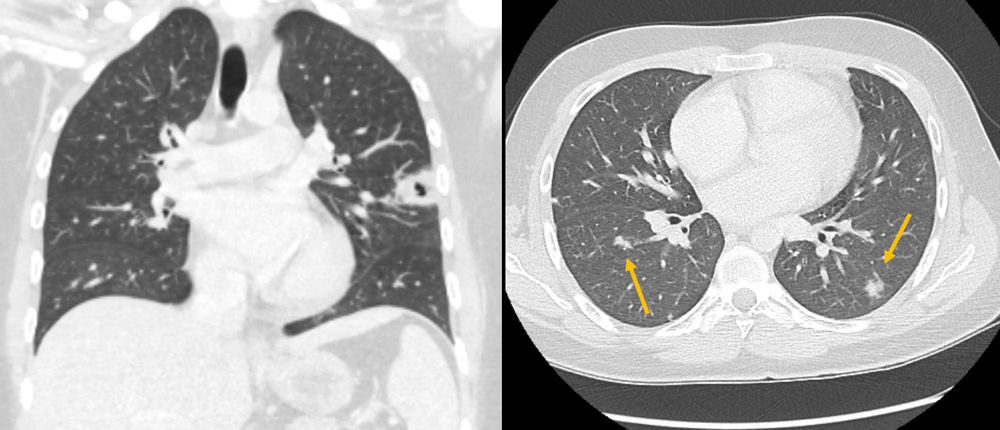

Sonographisch wird eine Thrombose der Vena jugularis interna (VJI) links festgestellt. Im Röntgenbild zeigt sich eine Kaverne im linken Oberlappen, in der Computertomographie weitere Rundherde in allen Lungenlappen.

Wenn der Verdacht besteht, sollen Blutkulturen möglichst während der Fieberphase asserviert werden. Zusätzlich sollte eine Thrombose der VJI mittels Ultraschalls ausgeschlossen und eine Röntgenaufnahme vom Thorax zum Ausschluss einer pneumogenen Ausbreitung durchgeführt werden.